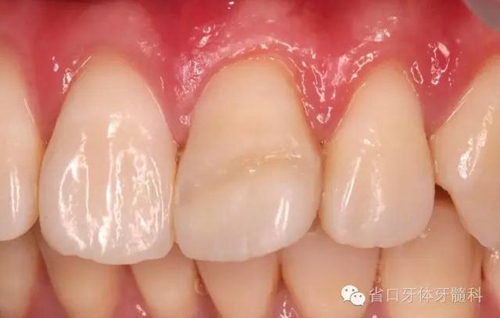

患者1個(gè)半月后復(fù)診,口腔衛(wèi)生狀況保持良好,牙齦健康,折斷線不可見。

斷冠再接優(yōu)勢(shì):快速恢復(fù)美觀,降低患者創(chuàng)傷后心理傷害,容易被患者接受;花費(fèi)低、操作簡(jiǎn)單。不適用粉碎性冠折,遠(yuǎn)期臨床效果有待進(jìn)一步觀察。

本病例不足:治療步驟可進(jìn)一步優(yōu)化:先行牙周治療,徹底清理牙結(jié)石;其次根管治療;等待齦溝滲血停止后,橡皮障隔離下行斷冠再接,粘接強(qiáng)度會(huì)更有保障;本病例進(jìn)一步隨訪中。